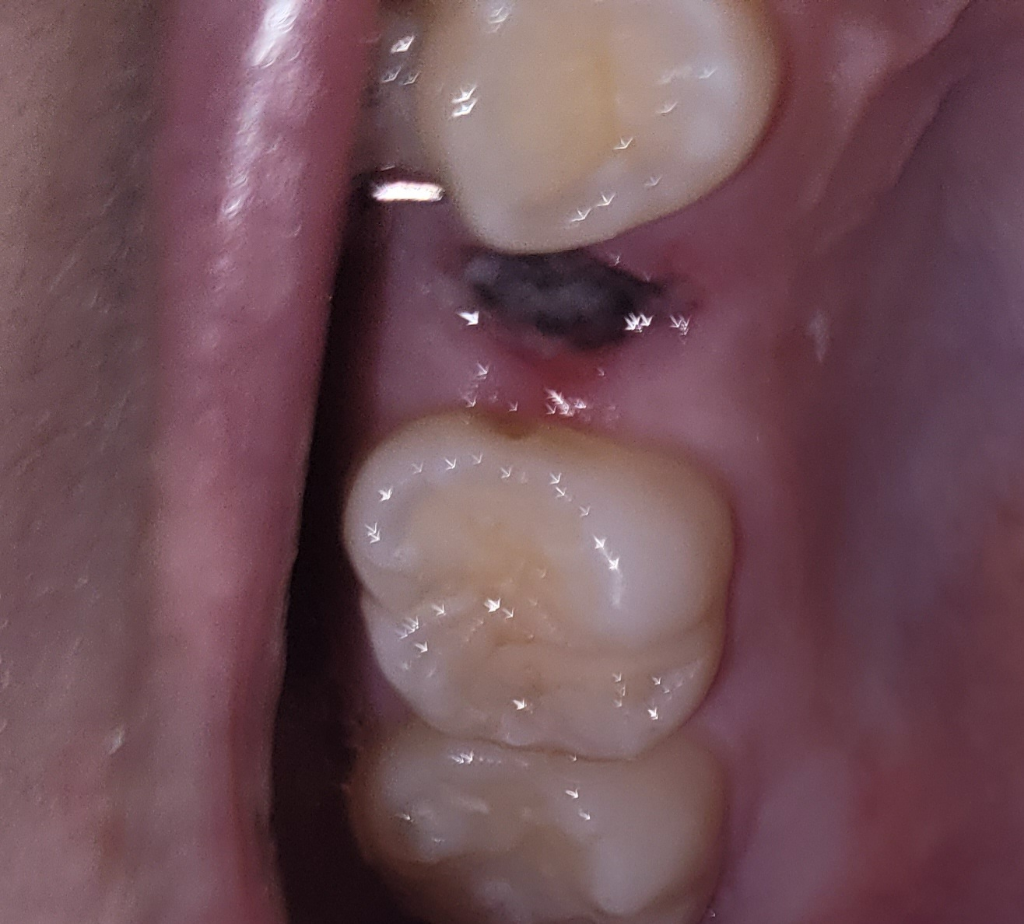

치아 발치 후 잘 아물고 있는지 확인해주실 수 있나요?

상악 작은어금니 발치 후 55시간 정도 지난 상태인데 잘 아물고 있는지 확인 부탁드립니다

겉부분에 곰팡이처럼 생긴게 있는데 저게 뭔지, 안 좋은건지 궁금합니다 입을 계속 헹궈도 사라지지 않던데 건드리지 않는게 좋을까요?

• 2번 째 사진

하얗게 막이 생기는 것은 낫기 위한 과정입니다. 일부러 건드리지 마시고 주의사항 지켜주면 됩니다.

사진상으로 보면 잘 아물고 있는거 같습니다. 일주일정도는 최대한 발치한곳에 자극이 가지 않도록 해주세요.

사진으로만 봤을 경우에는 혈병을 잘 형성되고 아물고 있는 것으로 보입니다.

발치를 한 부위를 자극하게 되면 출혈이 되고 치유가 늦어질 수 있기 때문에 발치를한 부위는 건들지 않는 것이 좋습니다.

잘아물고 있는 것으로 보이며, 혈병이 생기고 있는 것으로 일부러 떼어나거나 하지 말고 그대로 두시면 됩니다.